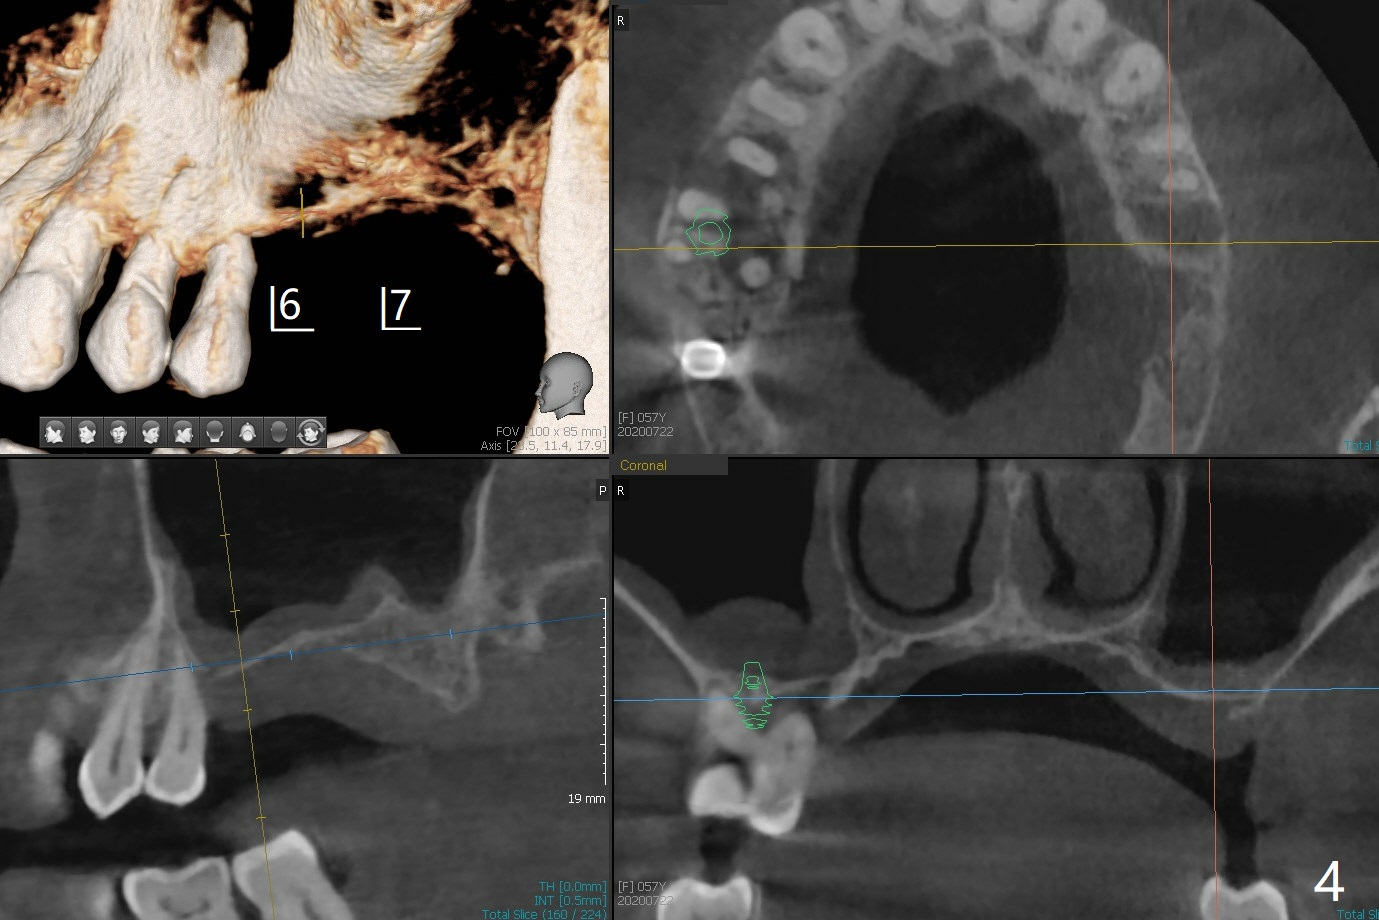

57岁女严重牙周炎,主诉右上磨牙食物堵塞(图一:圆圈)。第一磨牙骨质吸收,松动,需要拔除,尽管骨壁2-3毫米(图二),使用导航应该能取得5乘7.3毫米植体(图三绿色)初步稳定性。上颌窦膜厚,提升术不容易破裂,使用PRF膜预防及修补。由于近中骨质缺损严重(图三 *),植体可以再提高些(箭头),利用粘性骨做提升以及骨质缺损充填,似乎颊侧骨质多些(图五),植体可以小些,万一不行,就做提升和植骨。左上磨牙区骨壁更薄(图四,约1毫米),外提升术之后再种植。